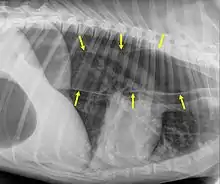

Megaesophagus

Megaesophagus, also known as esophageal dilatation, is a disorder of the esophagus in humans and other mammals, whereby the esophagus becomes abnormally enlarged. Megaesophagus may be caused by any disease which causes the muscles of the esophagus to fail to properly propel food and liquid from the mouth into the stomach (that is, a failure of peristalsis). Food can become lodged in the flaccid esophagus, where it may decay, be regurgitated, or may be inhaled into the lungs (leading to aspiration pneumonia).